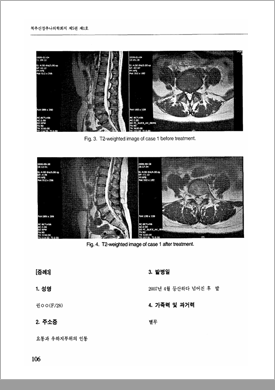

2010년 발표한 논문을 통해 척추수술실패증후군 (FBSS)과 같은 중증 허리디스크 질환도 한방치료만으로 치료가 가능하며,

수술과 달리 재발 위험이 낮다는 치료 결과를 입증하였습니다.

2010년 발표한 논문을 통해 심한 허리통증으로 요추 4/5번 추간판탈출증 진단을 받은 환자에게

추나요법을 비롯한 한방치료로 통증이 크게 호전되었다는 치료 결과를 입증하였습니다.

2010년 발표한 척추신경추나의학회

척추측만증 논문